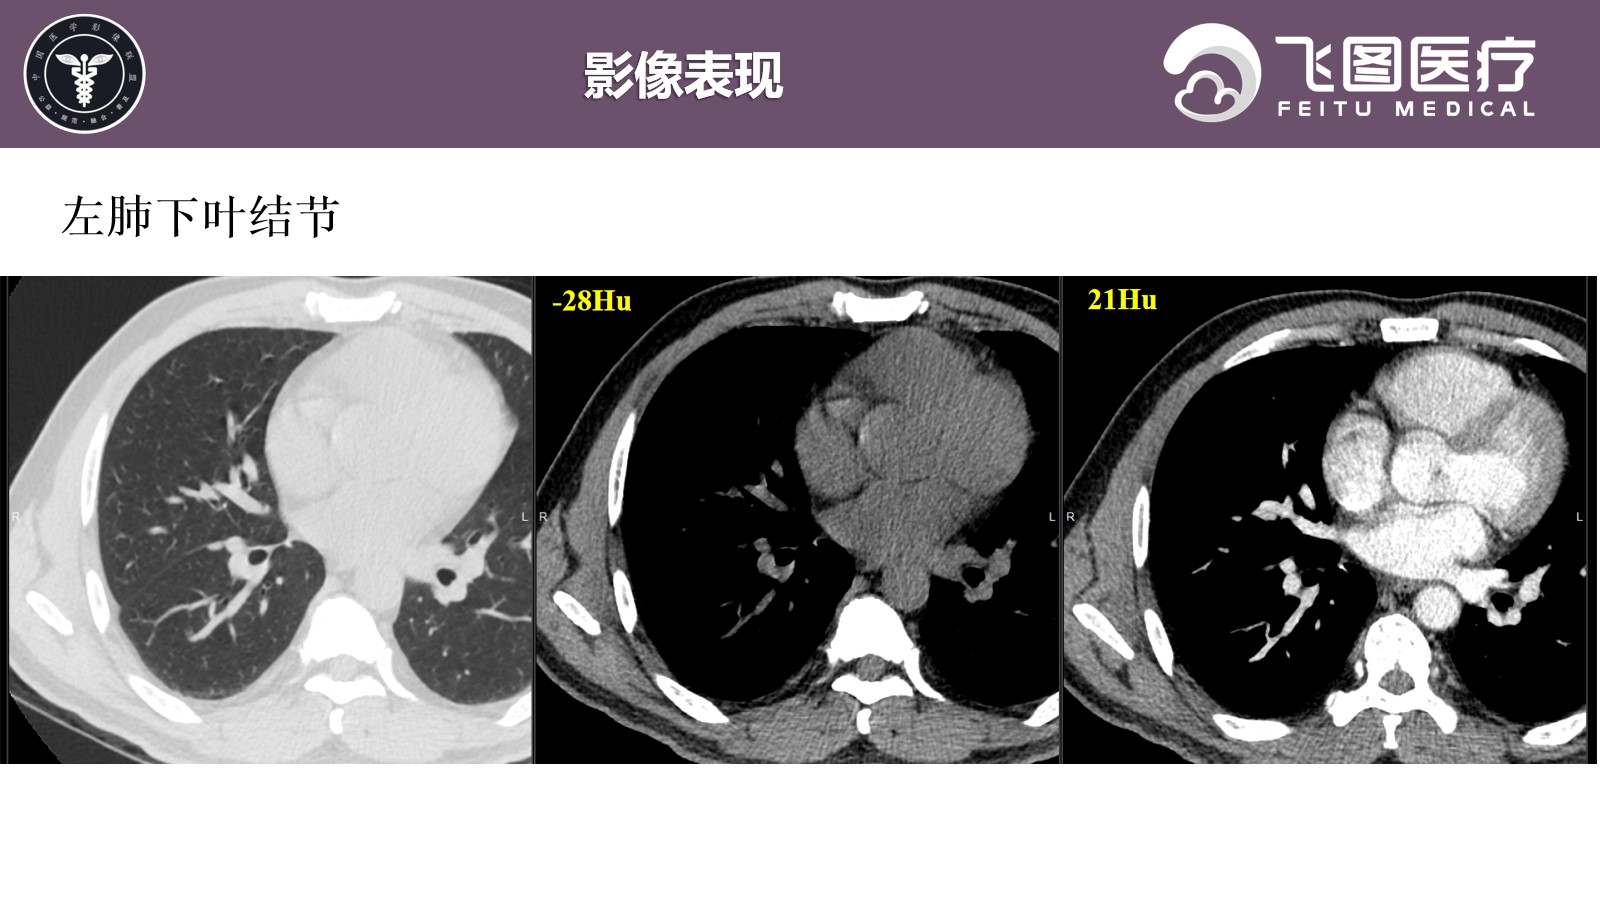

患者,男,50岁,因“检查发现右上纵隔肿物1月余。”入院。

现病史:患者于1月余前因“胆囊结石并胆囊炎”于我院治疗。查胸部X片提示右肺尖区斑片状密度增高影,倾向后纵隔来源占位性病变。患者平素无咳嗽、咳痰,无胸闷、气促,无呼吸困难等。

既往史:因“胆石症”行“腹腔镜下腹腔粘连松解+胆囊切除术”,术后病情较前好转,复查无异常,出院诊断: 1.胆囊结石伴有急性胆囊炎; 2.胆囊息肉; 3.黄疸; 4.肝功能检查的异常结果; 5.纵隔肿物; 6.肺结节; 7.脾大; 8.轻度贫血。